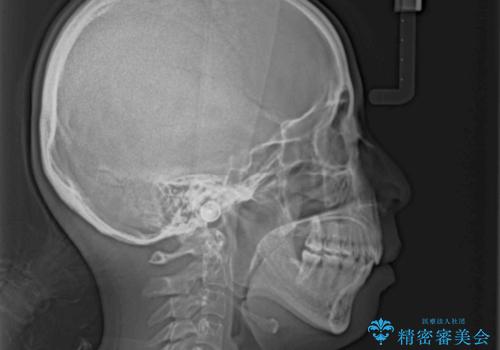

Eラインを改善したい ハーフリンガルによる抜歯矯正

- 口元の突出感を気にして来院された患者様です。

上下左右の第一小臼歯4本を抜歯して口元を下げる治療計画としました。

舌の突出癖が強く、口元を引っ込める力に拮抗してしまい、抜歯スペースを閉じるまでに時間がかかりました。

また途中出産もありましたが、無事に治療を終えることができました。